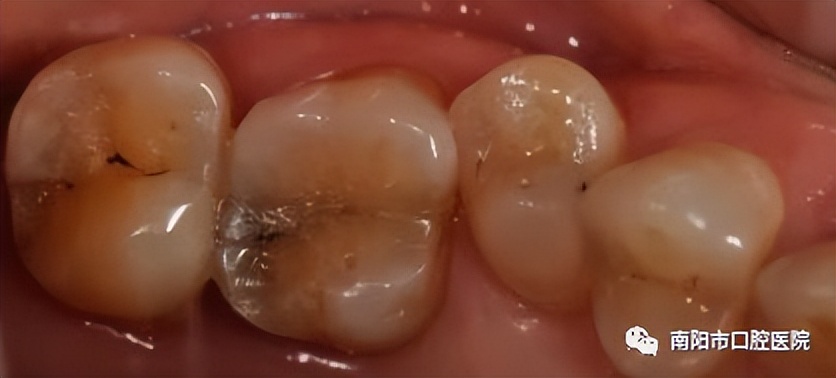

树脂充填治疗